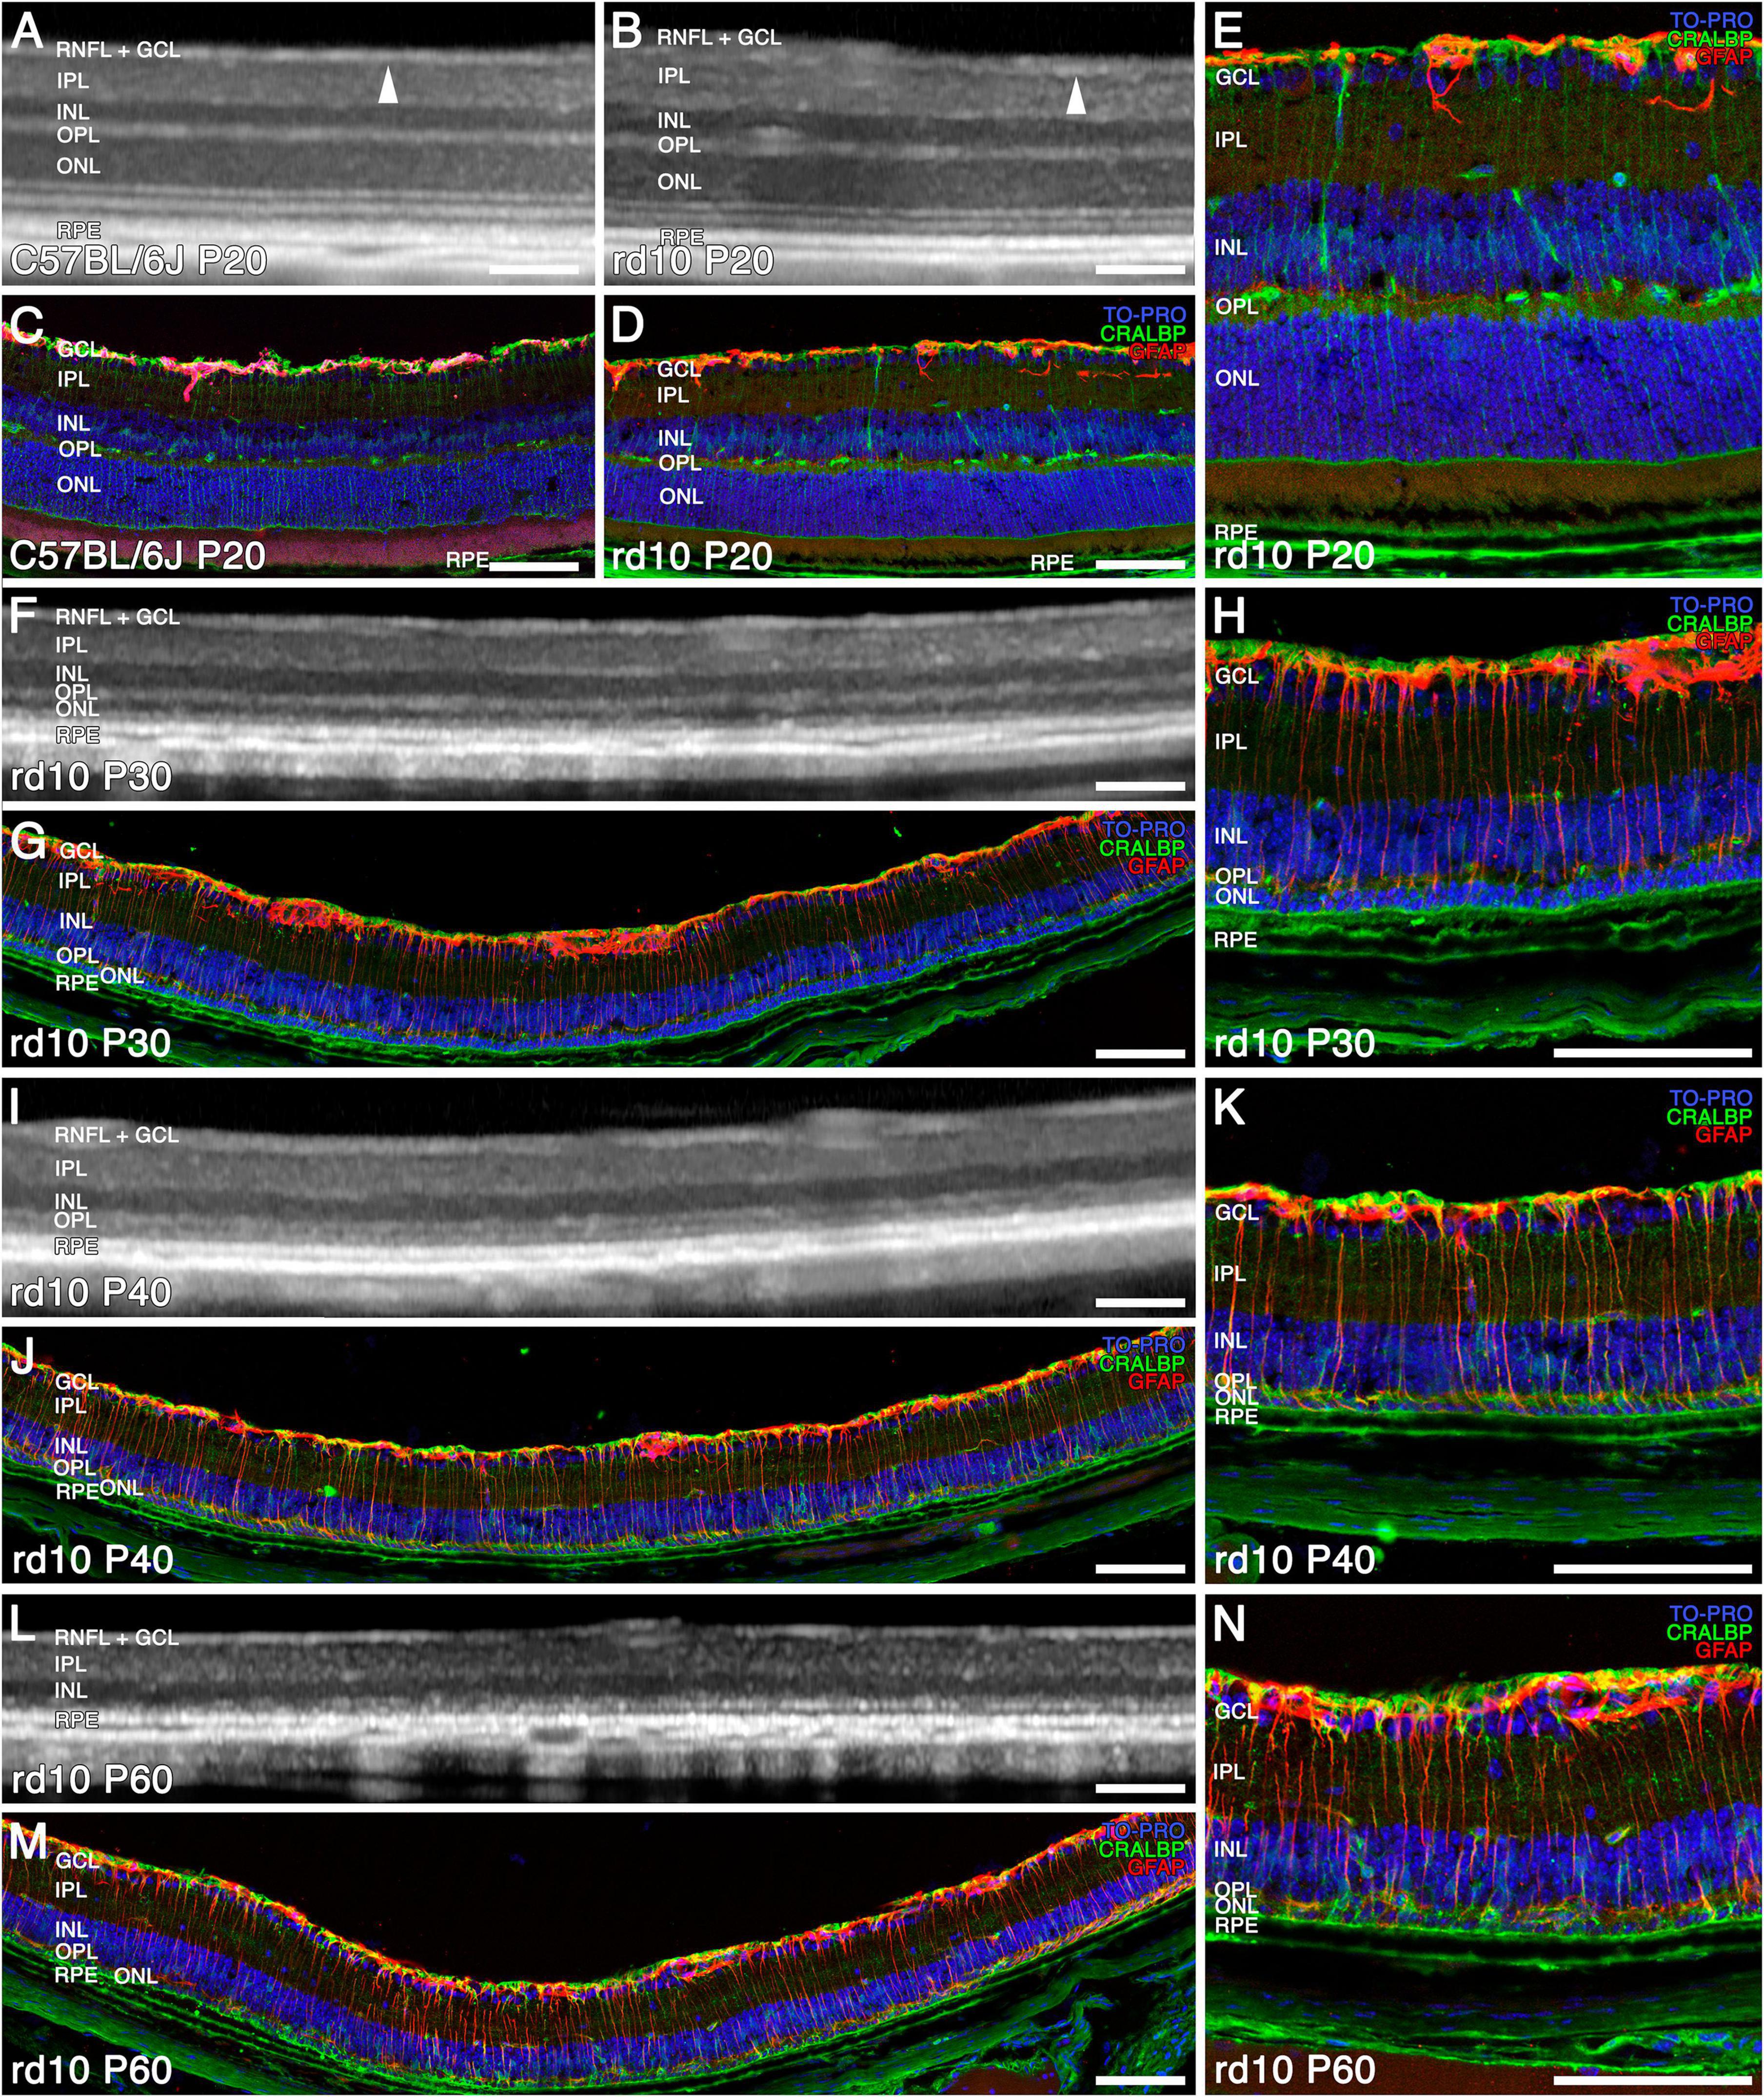

The OCT was utilized to assess the retinal structure of rd10 mice and correlate these findings with immunohistochemical analyses of age-matched retinas (Figures 1, 2). At P20, OCT images of rd10 retinas revealed a hyperreflective banding pattern similar to that observed in wild-type mice (Figures 1A, B). Within the inner retina, the retinal nerve fiber layer (RNFL) appeared as a distinct hyperreflective band, separable from the ganglion cell layer (GCL) and the inner plexiform layer (IPL) (Figures 1A, B, arrowheads). The inner nuclear layer (INL), and the outer nuclear layer (ONL), were discernible as two hyporeflective bands separated by a hyperreflective band corresponding to the outer plexiform layer (OPL). The outer retina exhibited four distinct hyperreflective bands, indicative of the structural compartments of photoreceptors and the retinal pigment epithelium (RPE) (Figure 1A). However, in the case of the rd10 group, the third and fourth outer bands could not be reliably distinguished (Figure 1B). Histological analysis corroborated these findings, demonstrating well-preserved retinal layering in C57BL/6J and rd10 mice (Figures 1C–E). Immunohistochemical staining with anti-CRALBP antibodies identified Müller cells and the RPE (green), whereas anti-GFAP antibodies labeled astrocytes (red). Nuclei were counterstained with TOPRO (blue) (Figures 1C–E).

Figure 1. Structural and morphological changes of C57BL/6J and rd10 retinas observed with OCT (A,B,F,I,L) and immunohistochemistry (C–E,G,H,J,K,M,N) from P20 to P60. Immunostaining of retinal sections shows Müller and RPE cells (CRALBP marker in green), astrocytes and reactive gliosis (GFAP marker in red), and nuclei (TO PRO marker in blue). General normal retinal structure in C57BL/6J (A) and rd10 (B) (arrowhead showing the limit between the RNFL + GCL and the IPL) and distribution of Müller cells and astrocytes at P20 (C–E). The ONL and the four outer hyperreflective bands are difficult to recognize from P30 to P40 with OCT (F,I), since the photoreceptors are already degenerating (G,H,J,K). The reactive gliosis is detectable at P30 and is maintained during the disease (H,K). At P60, both the ONL and the outer hyperreflective bands are indistinguishable (L) since photoreceptors have degenerated (M,N). Scale bars: (A–N) 100 μm.

By P30, OCT imaging revealed a pronounced reduction in ONL thickness, indicative of substantial photoreceptor loss (Figure 1F). At this stage, histological examination revealed that only two rows of photoreceptor nuclei remained, highlighting a more advanced stage of retinal degeneration compared to P20 (Figures 1E vs 1H). Furthermore, the hyperreflective bands within the outer retina exhibited significant disorganization, consistent with the degeneration of photoreceptors and the progressive disruption of their inner and outer segments (Figure 1F). Immunohistochemical analysis further confirmed these degenerative changes in the ONL, characterized by the depletion of photoreceptor cell bodies and the loss of their inner and outer segments (Figures 1G, H).

From P40 onward, the ONL becomes nearly imperceptible in OCT images (Figure 1I), as only a single row of photoreceptor nuclei remains, as confirmed by TOPRO staining in immunohistochemical analyses (Figures 1J, K). Furthermore, the four outer hyperreflective bands observed in OCT progressively lose their distinction, appearing similar to those seen at P30 (Figures 1F, I). At this stage, the inner retina does not exhibit a significant reduction in thickness.

By P60, the outer hyperreflective bands merge with the remnants of the OPL, rendering them indistinguishable (Figure 1L). The ONL band itself becomes unrecognizable in OCT imaging (Figure 1L), and the immunohistochemical analysis at this time point reveals only a sparse population of remaining photoreceptor nuclei in the ONL (Figures 1M, N).

This degenerative process, which we observed from P30, is accompanied by a progressive increase in GFAP immunoreactivity (red), indicative of reactive gliosis in Müller cells and astrogliosis. This glial response intensifies as retinal degeneration advances, as observed in immunohistochemical images (Figures 1E vs 1H, K, N).